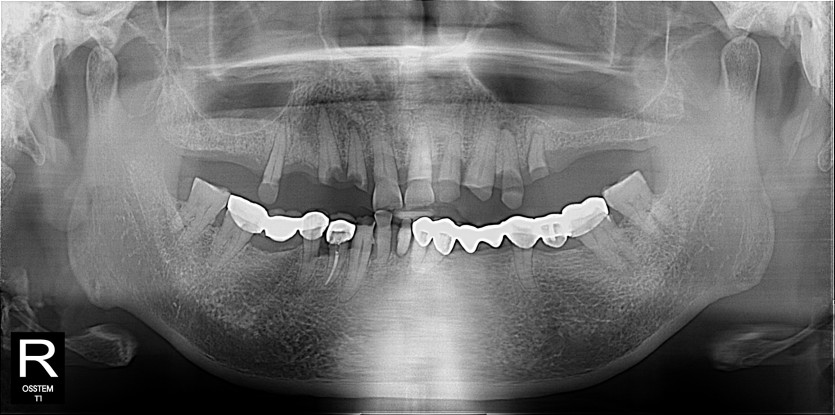

임플란트 사례